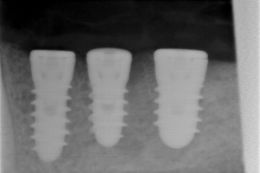

Il paziente è in attesa di impianti nel 4 quadrante mentre nel 3 quadrante sono stati inseriti i primi 3. Aggiorneremo le foto a caso finito.

Secondo noi questa risulta essere la procedura corretta per il recupero di spazio implantare in soggetti adulti prima di un trattamento implantare, correggendo la inclinazioni sbagliate con un uprighting ortodontico.

Caso condotto in collaborazione con la Dott.ssa Laura Marchione.